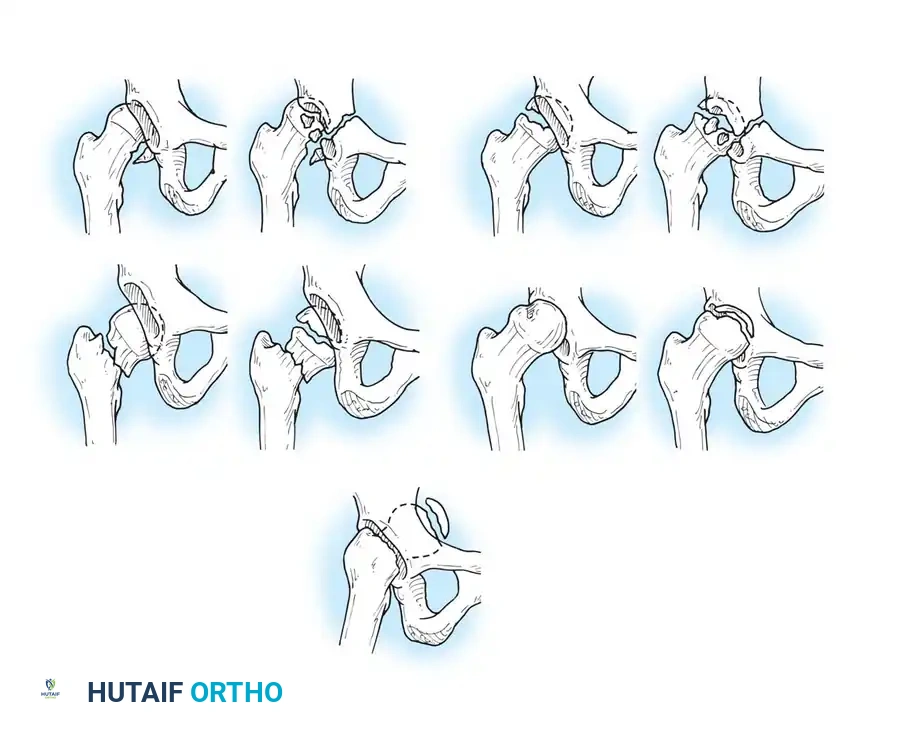

Thompson and Epstein Classification

For posterior dislocations, the Thompson and Epstein classification remains a foundational framework, dividing these injuries into five distinct types:

- Type I: Dislocation with or without a minor fracture.

- Type II: Dislocation with a large single fracture of the posterior acetabular rim.

- Type III: Dislocation with comminution of the posterior acetabular rim, with or without a major fragment.

- Type IV: Dislocation with fracture of the acetabular floor.

- Type V: Dislocation with fracture of the femoral head.

Diagrammatic representation of various hip fracture-dislocation patterns highlighting the relationship between the femoral head and acetabular rim.

Further classification of femoral head fractures associated with posterior hip dislocations, emphasizing the location of the fracture relative to the fovea capitis.

While this classification system was formulated before the widespread advent of Computed Tomography (CT), it remains conceptually vital. Historically, Thompson and Epstein recommended routine open reduction for all fracture-dislocations to clear retained fragments. Today, high-resolution CT allows for precise preoperative identification of retained osteocartilaginous fragments, guiding the decision between closed management and operative intervention.